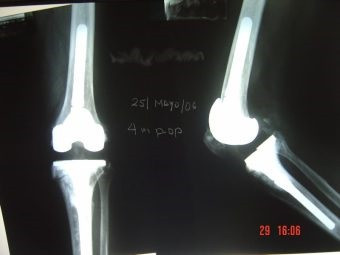

Revisión de prótesis de rodilla

Envíado por Dr. Ricardo Antonio Gómez G.